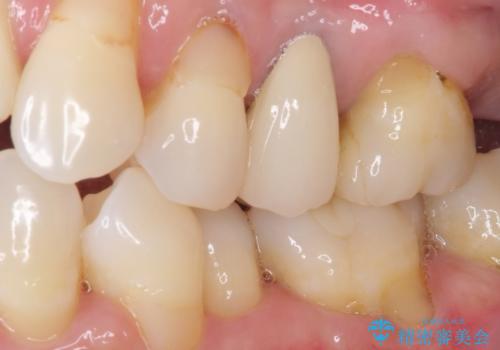

仮歯に変えた後にオールセラミッククラウンにて補綴することとしました。

治療前と比べてとても自然な前歯となり、患者様には大変満足していただきました。